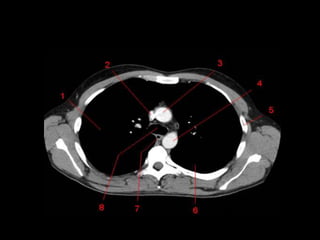

TC mediastino superior